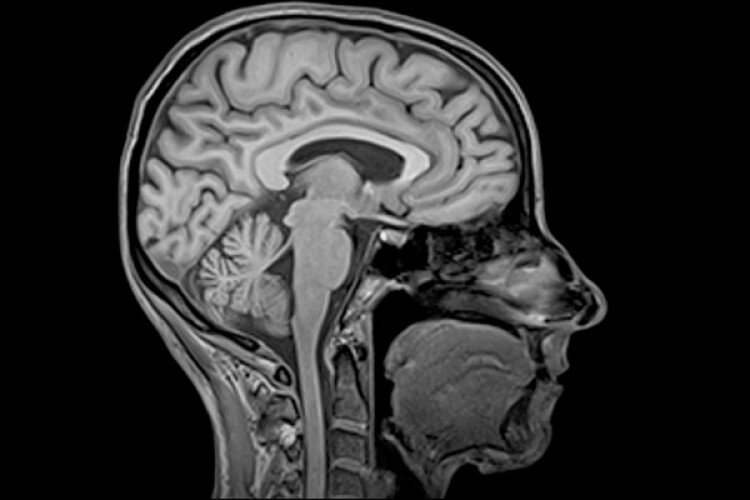

МРТ и КТ - обследования, способные посмотреть, что происходит в голове. Если вас мучают периодически возникающие головные боли, казалось бы не из-за чего обязательно посетите невропатолога и сделайте МРТ. Не всегда невропатолог даёт направление на МРТ, для этого ему нужны веские основания. По этому, если у вас есть возможность сделайте МРТ в частном порядке, дабы удостовериться в отсутствии или выявить вовремя заболевание.